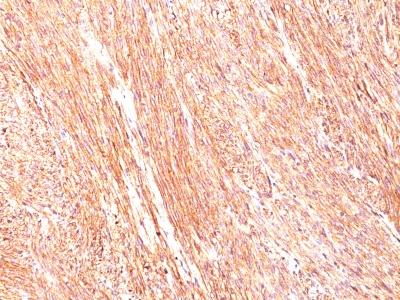

Monoclonal Antibody to DOG-1 / TMEM16A (Gastrointestinal Stromal Tumor Marker)(Clone : DG1/447)

Formalin-fixed, paraffin-embedded human GIST stained with DOG1 Monoclonal Antibody (DG1/447).